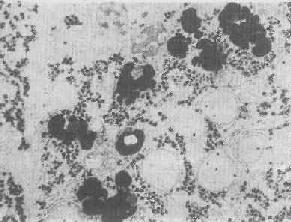

图1-14 肝细胞内次级溶酶体

贮存在溶酶体中的物质被溶酶体酶加以降解(消化)。但有时进入细胞的物质为量过多,超过了溶酶体的处理能力,于是乃在细胞内贮积,例如各种原因引起的蛋白尿时可在肾近曲小管上皮细胞中见到玻璃滴状蛋白质的贮积(所谓玻璃样小滴变性)。在电镜下可见这种玻璃样小滴乃载有蛋白质的增大的溶酶体,故实质上这往往是细胞功能增强的表现,与真正的变性有所不同。

图1-15 肝细胞内脂褐素颗粒残存小体即终末溶酶体